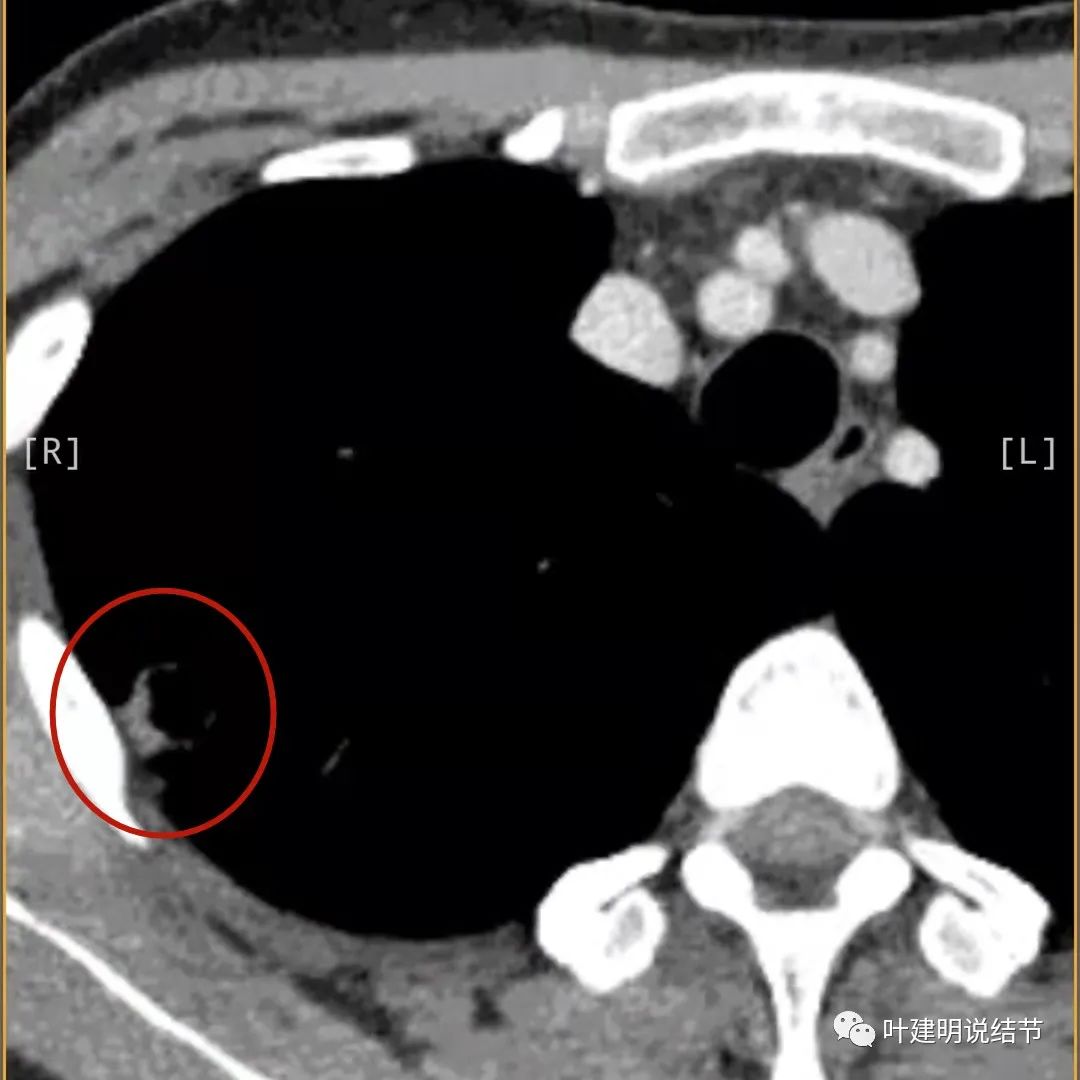

上图病灶边缘比较平直,没有膨胀性(桔色箭头),旁边的磨玻璃影淡且界限不清,邻近胸膜增厚。

再看影像印象:病灶较1年前有所进展,部分层面像恶性,囊壁厚薄不均,内面有小突起。但邻近胸膜增厚,旁边的磨玻璃部分散且淡,边界不清,实性部分边相对较光,囊壁有点状过高密度。良性可能性大些,恶性不能除外。